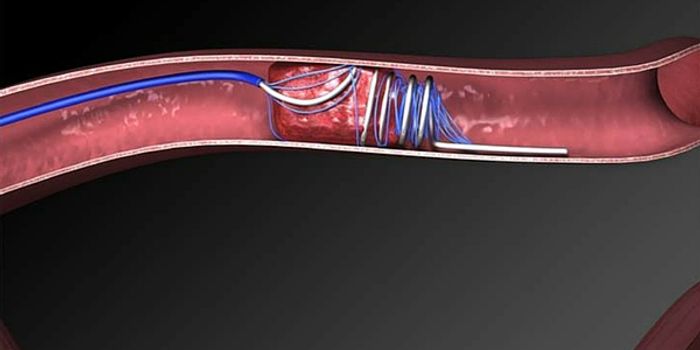

MAR 21, 2016NeuroscienceThe most common kind of stroke, an ischemic stroke, is caused by a blood clot which blocks the flow of oxygenated blood ...